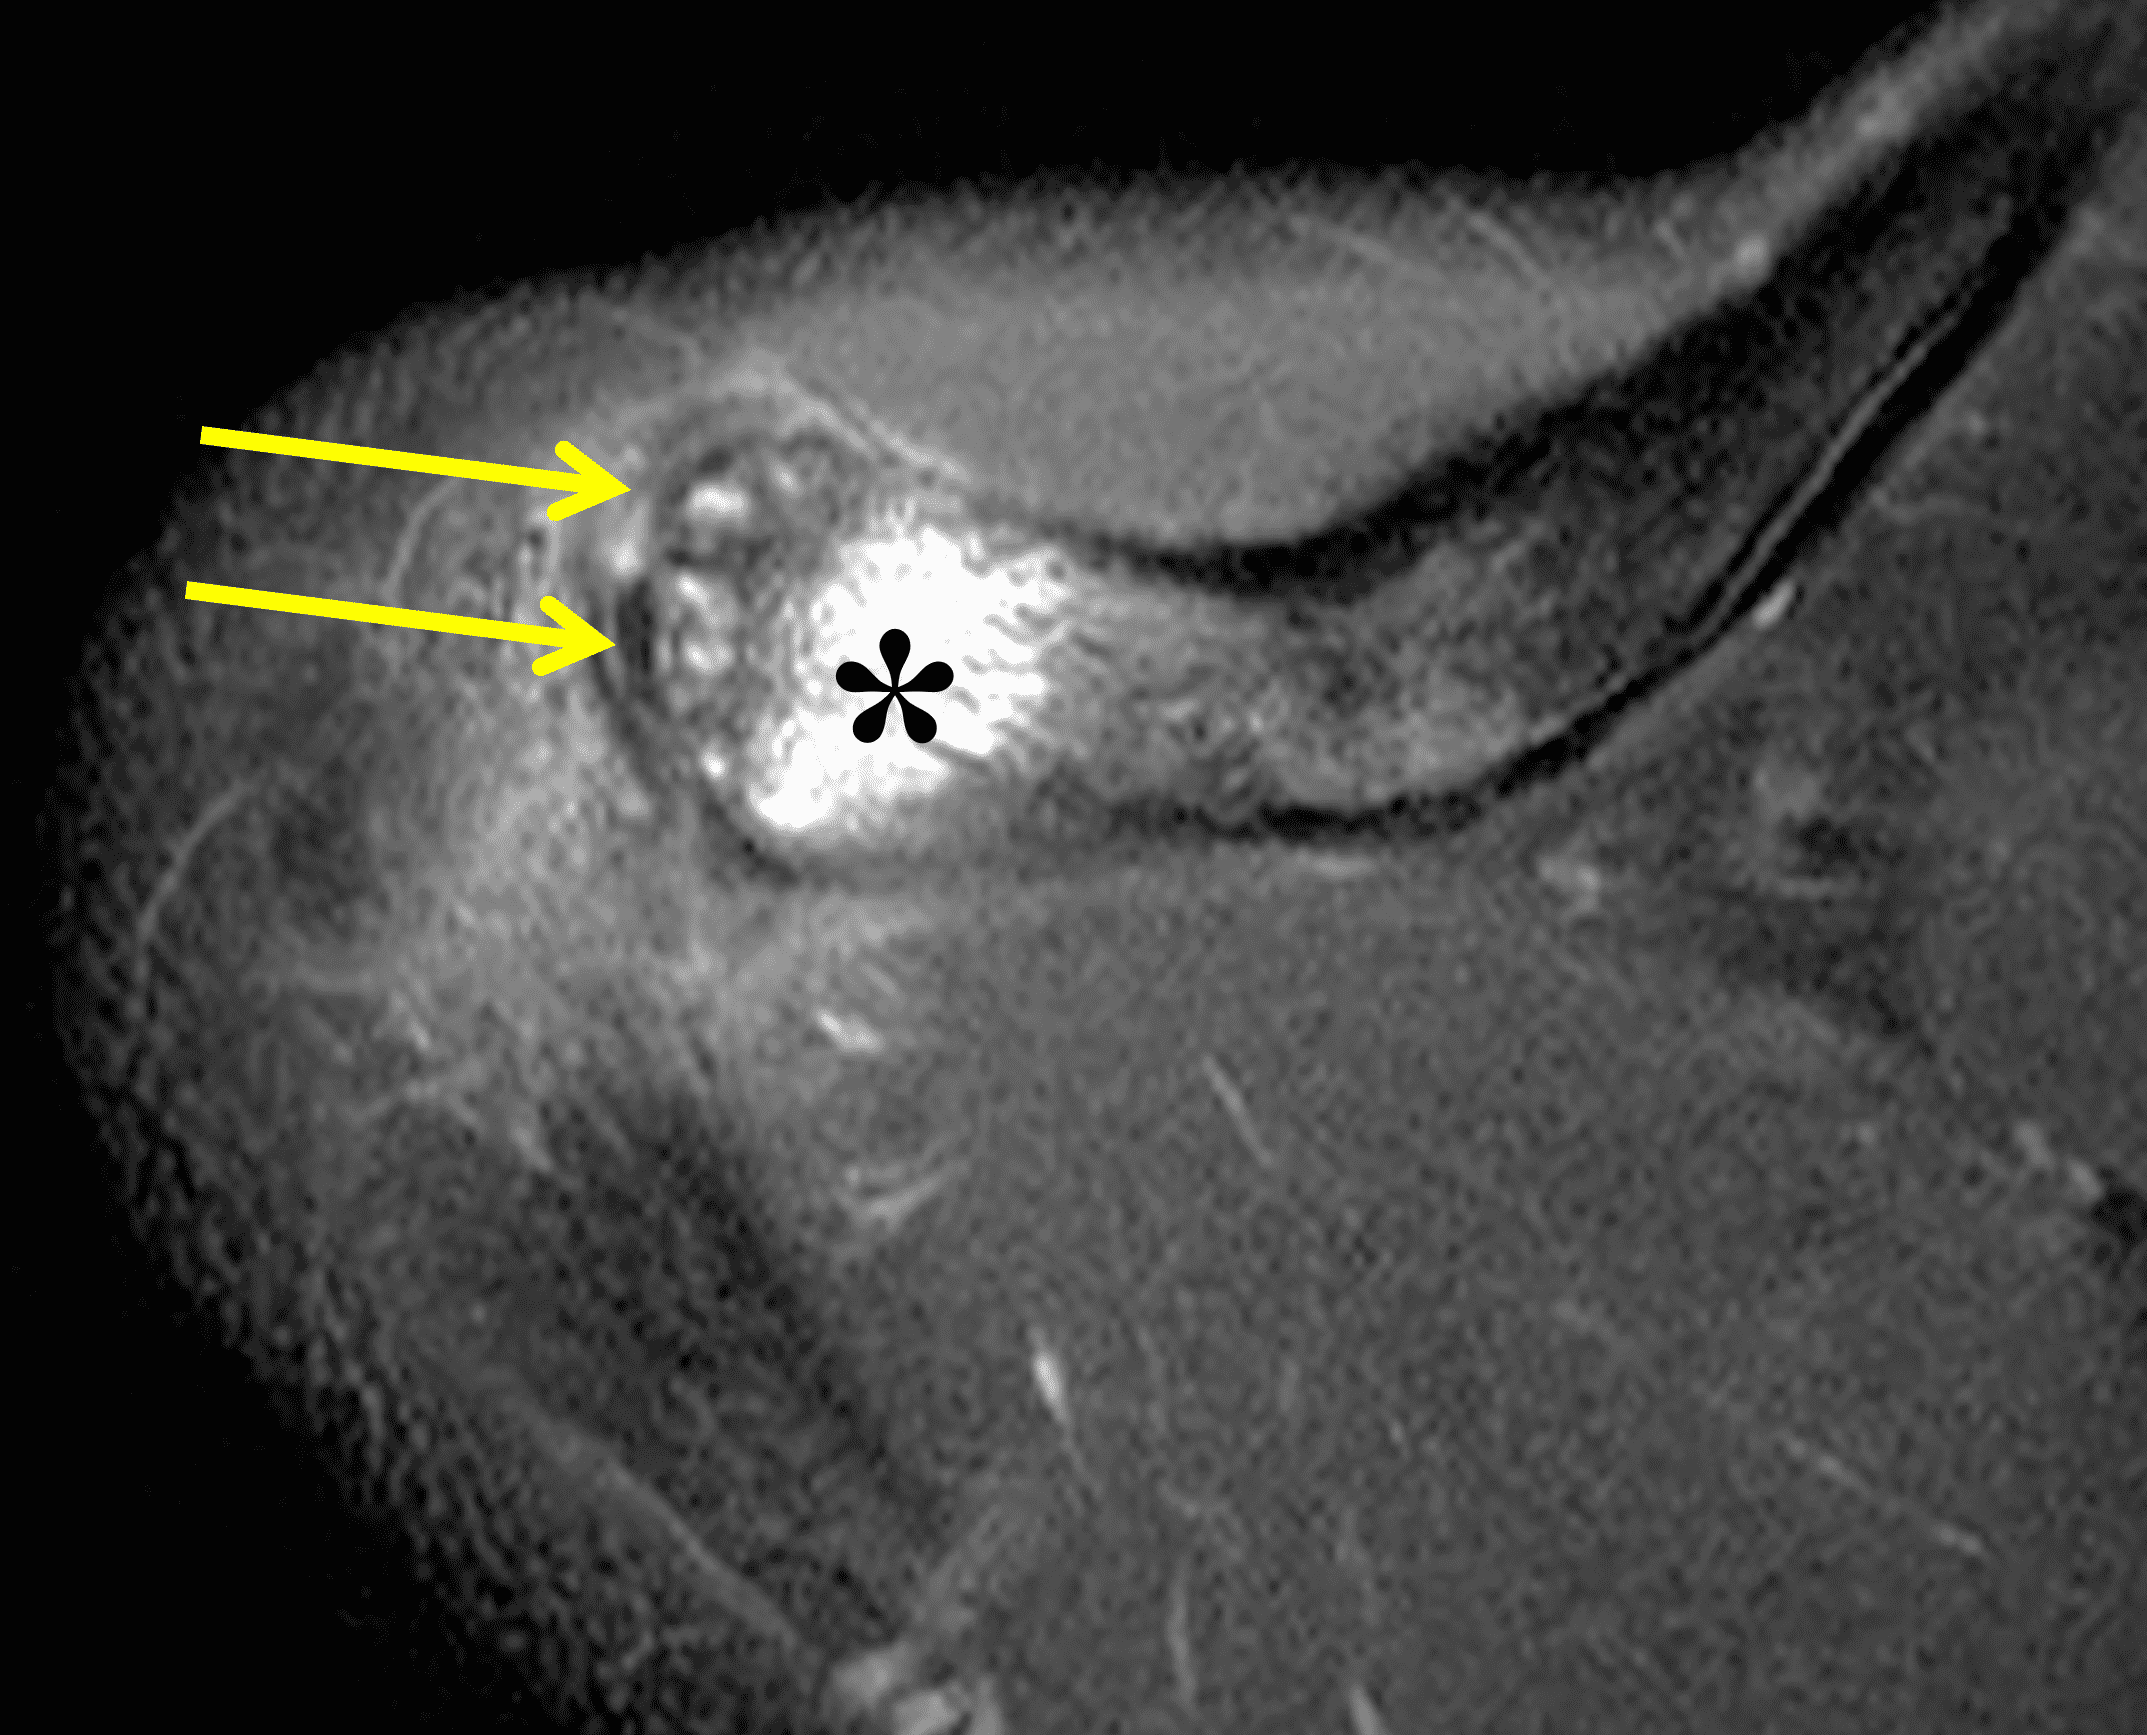

Radiographs: Initial radiographs may be normal or show features of other common unrelated AC joint pathology such as osteoarthritis. As inflammation and hyperemia in the distal clavicle progresses, bone density in the distal clavicle can decrease with indistinctness or discontinuity of the subchondral bone plate (Figure 3).  This so-called resorptive phase may also include frank erosions in the distal clavicle or a faint sclerotic line in the medullary space of the distal clavicle parallel to the bone end. Varying degrees of surrounding soft tissue swelling may be visible.  Later, during the late healing phase when symptoms have usually resolved, the distal clavicle may return to a normal radiographic appearance; a sclerotic line parallel to the distal bone end is visible after healing in some cases (Figure 4).  In patients with severe initial bone loss, re-cortication of the resorbed bone and erosions can occur leaving residual bone loss and contour defects in the distal clavicle. While it is typically not a primary modality for the diagnosis of DCO, CT demonstrates the same bone findings as radiographs.

The principle MRI finding of DCO is distal clavicular marrow edema and surrounding inflammation on fluid-sensitive pulse sequences, especially with fat suppression (Figures 3 and 4).2, 9 Marrow changes can occur in patients with normal radiographs,10 in which case a term like “stress/overuse related marrow edema,” might be preferable to “osteolysis.” On MRI, more severe cases may show erosions or cysts in the distal clavicle and loss of the subchondral bone plate in addition to more pronounced marrow and soft tissue edema. A band of low signal paralleling the distal bone end may be present, suggesting a stress fracture line (Figure 5).8 However, a similar appearance can be due to the sclerotic rim surrounding distal clavicle cysts or small erosions (Figure 6). A small effusion or mild synovitis is often present in the AC joint.  Soft tissue edema within and surrounding the AC joint capsule and distal clavicular periosteum may be visible (Figure 3).  Some patients may also show marrow edema (or even erosions) in the anterior acromion, but the changes are typically more severe in the distal clavicle (Figures 5 and 7).2